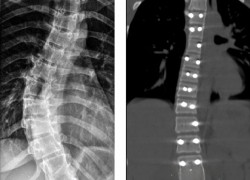

Опухоль из позвоночника через крошечный разрез удалили пациентке нейрохирурги Пятигорска

Почти год мучилась 28-летняя жительница Ставрополья от боли. Сначала у нее ныло в тазобедренном суставе, потом нога начала неметь, а затем появились проблемы...